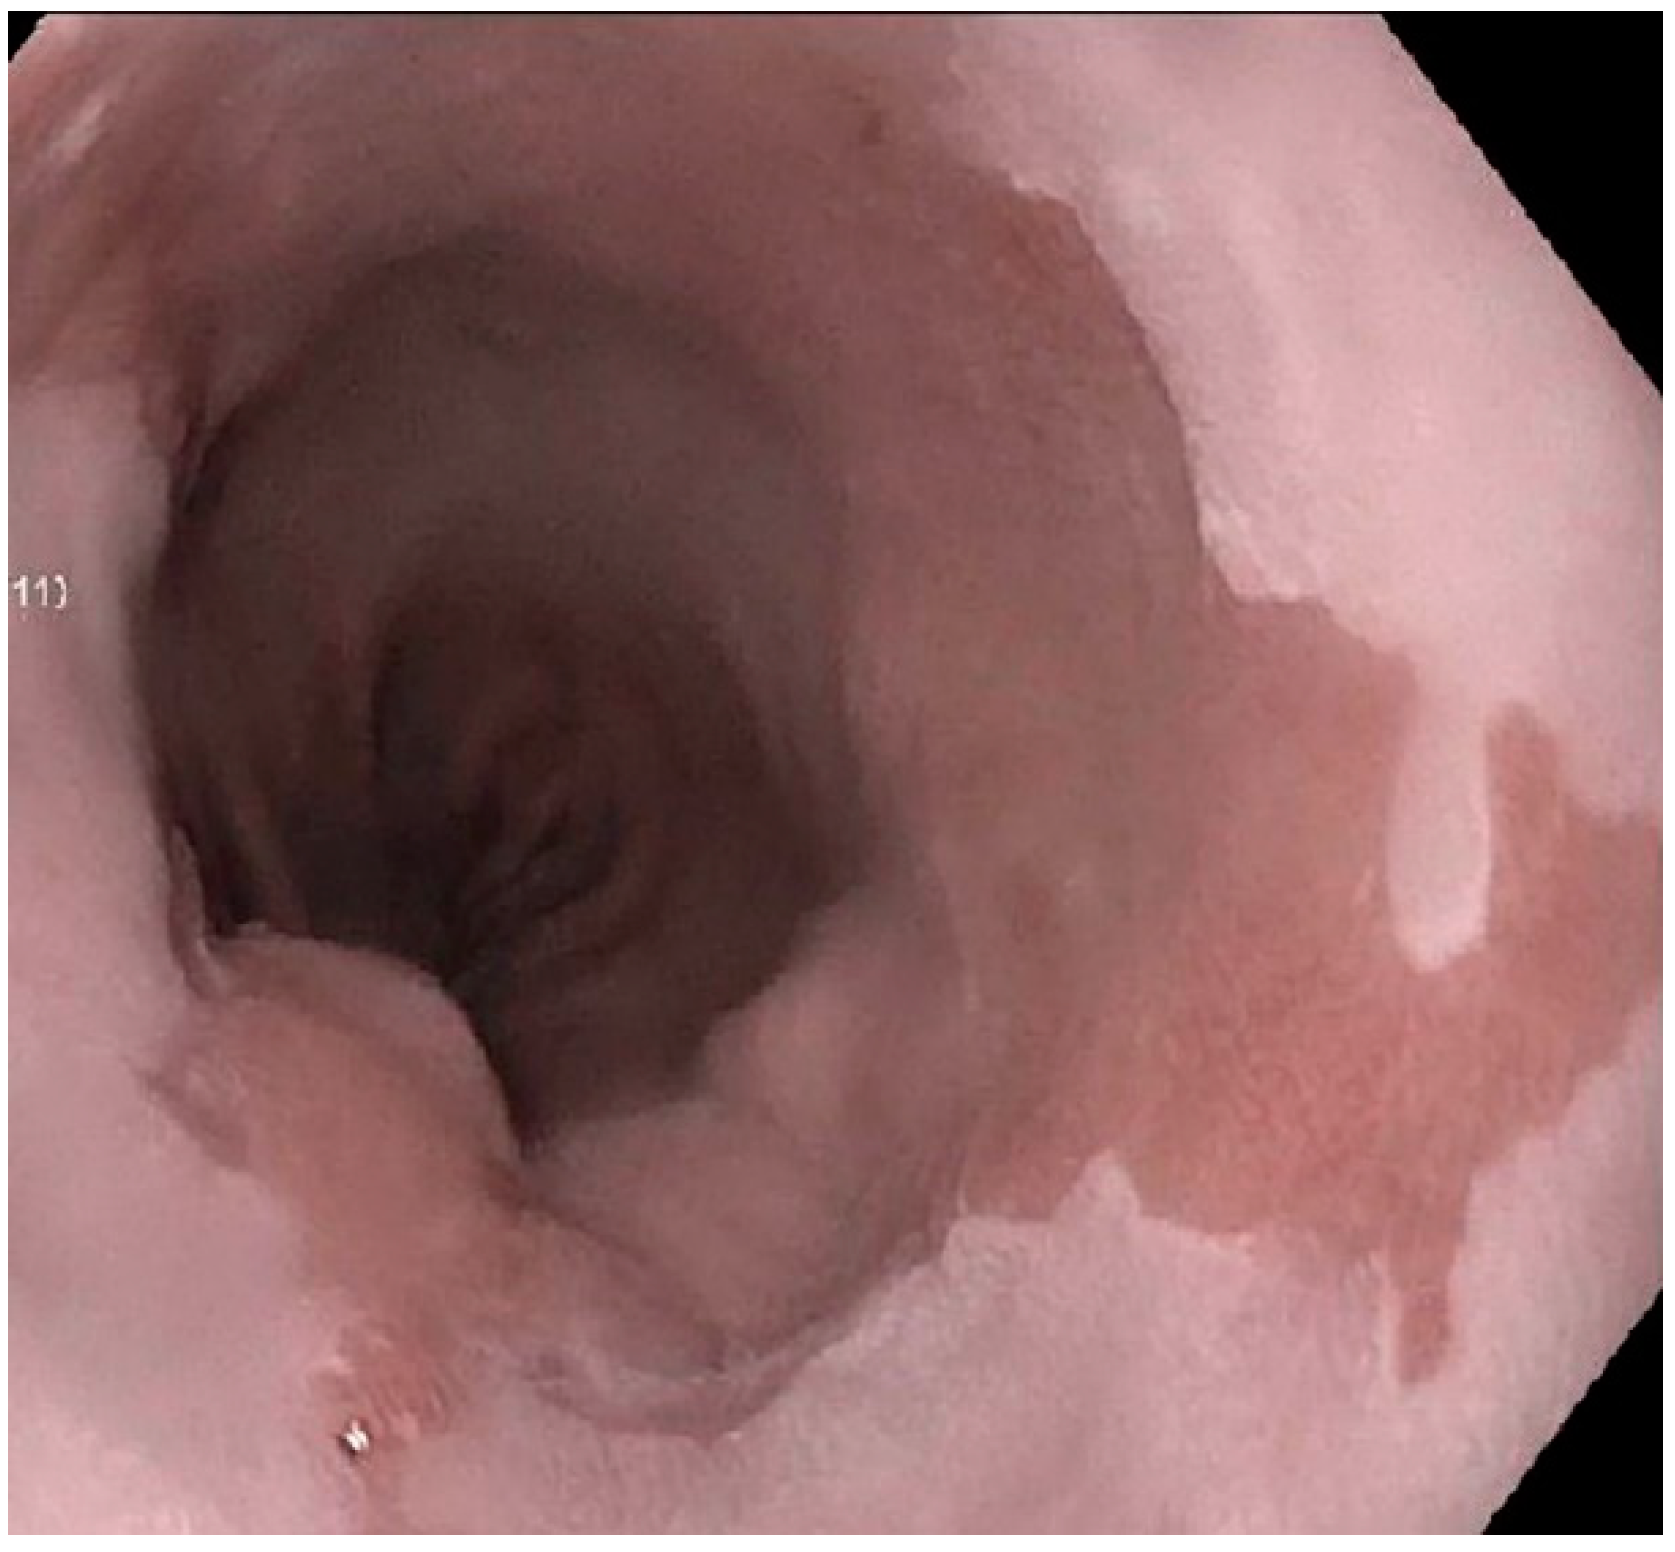

Barrett's Esophagus Endoscopy Findings. Barrett's esophagus is a condition affecting the lining of the esophagus, the swallowing tube that carries foods and liquids from the mouth to the stomach. Observed in 92% of be resections, involving barrett mucosa, negative for dysplasia. Otherwise, the findings were robust to all sensitivity analyses. It focuses on new imaging technologies that increase our ability to. The controversy about be definition is still a problem amongst pathologist. Norman barrett, a british thoracic surgeon. No endoscopy report provided, there is intestinal. This video describes the basic approach to endoscopic inspection of barrett's esophagus. The condition was first described in 1950 by dr. Esophageal capsule endoscopy (ece) has recently been shown to be accurate in detecting barrett's esophagus. The diagnosis of barrett's esophagus rests upon seeing (at endoscopy) a pink esophageal lining that extends a short distance (usually less than 2.5 inches) up the esophagus from the gastroesophageal junction and finding intestinal type cells (goblet cells) on biopsy of the lining. Be is defined as the transition of normal. Since this original description, numerous advances. Although the risk of developing esophageal cancer is small, it's important to have regular checkups with careful imaging and extensive biopsies of the esophagus to check for precancerous cells (dysplasia). Barrett's esophagus is associated with an increased risk of developing esophageal cancer.

Prolonged exposure of the esophagus to the refluxate of gerd can erode the esophageal mucosa, promote inflammatory cell infiltrate, and ultimately cause epithelial necrosis. This tissue replacement is referred to as intestinal metaplasia. The diagnosis of barrett's esophagus rests upon seeing (at endoscopy) a pink esophageal lining that extends a short distance (usually less than 2.5 inches) up the esophagus from the gastroesophageal junction and finding intestinal type cells (goblet cells) on biopsy of the lining. Cancer risk is determined by the degree of dysplasia. Barrett's esophagus is associated with an increased risk of developing esophageal cancer. This condition often develops after years of experiencing gastroesophageal reflux. Since barrett esophagus is considered a premalignant lesion, confirmation with upper endoscopy and biopsy is warranted. Two years ago i was diagnosed with barrett's esophagus. However, most people with barrett's esophagus do not get cancer. So doctors recommend that people over the age of 50 with chronic doctors use a technique called endoscopy to diagnose and stage barrett's esophagus. No endoscopy report provided, there is intestinal. Barrett esophagus is well recognized as a complication of gastroesophageal reflux disease (gerd). Formulary drug information for this topic. Barrett's oesophagus itself usually causes no symptoms. Be is defined as the transition of normal. But barrett's esophagus increases the risk of esophageal cancer by 125 times. Prolonged exposure of the esophagus to the refluxate of gerd can erode the esophageal mucosa, promote inflammatory cell infiltrate, and ultimately cause epithelial necrosis. The controversy about be definition is still a problem amongst pathologist. How is barrett's esophagus diagnosed? Screening for barrett's esophagus is an upper endoscopy (a procedure in which, after being sedated, a camera attached to a long, thin tube is inserted into the. Are there treatments that specifically target barrett's esophagus? Otherwise, the findings were robust to all sensitivity analyses. Additional risk factors include tobacco use and obesity. This often happens when cells are damaged by exposure to acid from the stomach. Barrett's esophagus is a condition in which the flat pink lining of the swallowing tube that connects the mouth to the stomach (esophagus) becomes damaged by acid reflux, which causes the lining to thicken and become red. Increased prevalence and radiographic findings. Barrett's oesophagus refers to metaplasia of the oesophageal epithelial lining, whereby normal stratified squamous epithelium is replaced by simple columnar epithelium. Observed in 92% of be resections, involving barrett mucosa, negative for dysplasia. Esophageal capsule endoscopy (ece) has recently been shown to be accurate in detecting barrett's esophagus. The annual incidence of progression to esophageal cancer is 0.12% to 0.33%; This altered tissue is similar to that which lines the intestine.